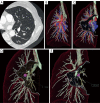

Figure 5

Segmentation of the pulmonary artery, vein and bronchus using 3D CT reconstruction (13). 3D, three-dimensional; CT, computed tomography. Available online: http://www.asvide.com/articles/869